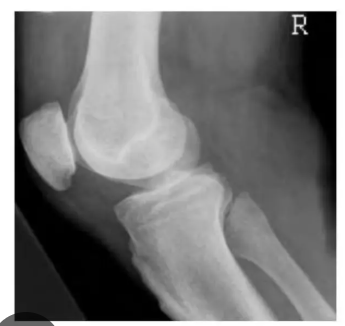

What projection?

Label?

Lateral knee

Femur

Superimposed medial and lateral condyles

Fibular head

Fibula

Femoropatellar joint

Intercondylar eminence

Tibia